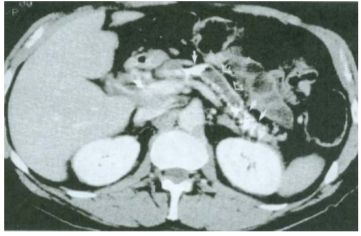

18. 45歲酗酒男性因慢性腹痛及解脂肪便(steatorrhea)接受腹部電腦斷層檢查(如圖示),下列何種併發症發生率最低? (A) 葡萄糖耐受不良(impaired glucose tolerance) (B) 糖尿病酮酸血症(diabetic ketoacidosis) (C) 胃腸出血 (D) 偽囊腫(pseudocyst) (E) 黃疸